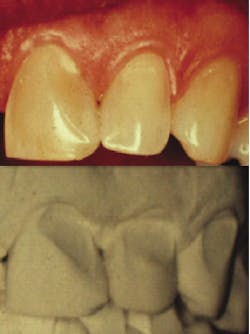

The objective of this paper is to stress the significance of making and retaining conventional diagnostic stone casts of a patient's mandible, maxilla, teeth, and the surrounding tissues. Full-arch diagnostic casts are valuable tools in determining various physiological and morphological changes that take place during the life span of the jaws, teeth, and periodontal tissues (Figs. 1-5).

Digital imaging impressions can also be used to make extremely accurate stone casts, which reproduce the jaws, teeth, gingival tissues, and palatal area (Fig. 6).1-4 Though the intraoral digital scanners are moving rapidly into the profession, use of conventional materials remain the most common source for making impressions. Stone casts are familiar to practitioners and, at this time, provide precise information on the bone, tissues surrounding the teeth, as well as their morphology and position. Use of stone casts can be an effective means of patient education, as they provide comparable observation of the changes that have taken place over time in the position and anatomy of teeth, bone, and soft tissues. A few noteworthy examples are demonstrated in Figs. 1-5.